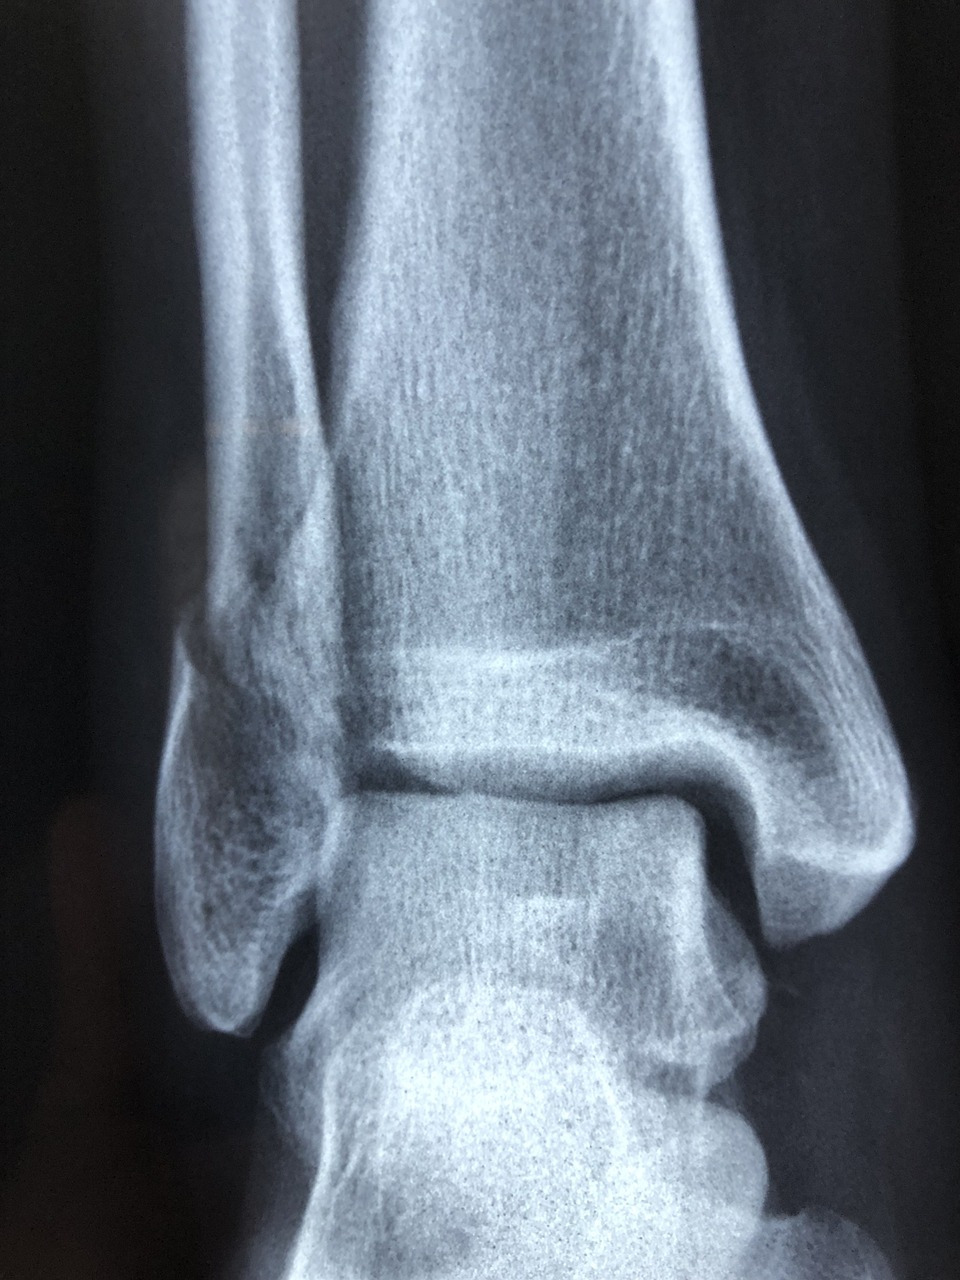

발목이라면 수 백 번 수 천 번 보셨을 의사 선생님 눈에도 확연히 굵은 내 딸의 발목 엑스레이는 명명백백했다. 나는 뺑덕어멈이 아니라 반의사였던 것이다. 아무 이상 없음이라는 진단과 동시에 아이의 통증은 사라졌고 아이는 4시 수업에 차질 없이 출석했다.

radiography-3057768_1280.jpg 출처: 픽사베이